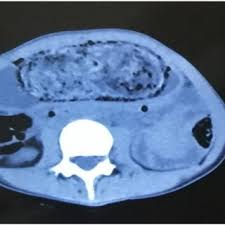

Computed Tomography Of The Abdomen And Pelvis Revealing A Massive Download Scientific Diagram